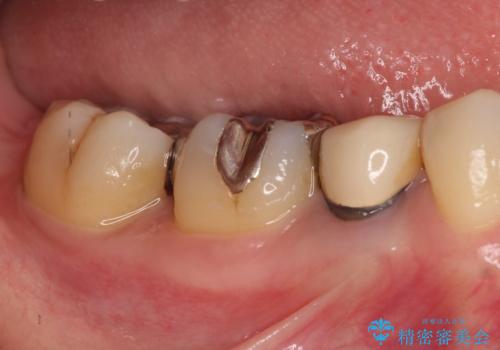

- 笑った時に見える金属を白くしたいとのことでメタルフリーの治療を希望され来院されました。

根管治療を行なったのち、オールセラミッククラウンにて修復処置を行っております。